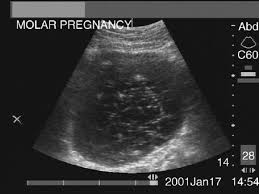

MOLAR PREGNANCY

MOLAR PREGNANCY studylib.net